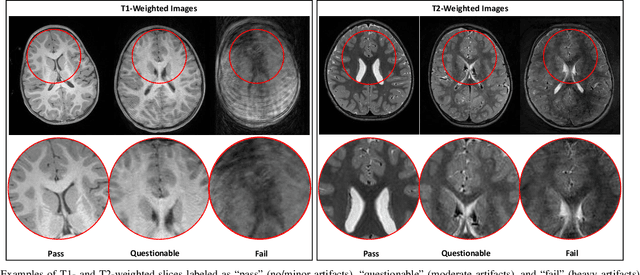

Abstract:In this paper, we introduce an image quality assessment (IQA) method for pediatric T1- and T2-weighted MR images. IQA is first performed slice-wise using a nonlocal residual neural network (NR-Net) and then volume-wise by agglomerating the slice QA results using random forest. Our method requires only a small amount of quality-annotated images for training and is designed to be robust to annotation noise that might occur due to rater errors and the inevitable mix of good and bad slices in an image volume. Using a small set of quality-assessed images, we pre-train NR-Net to annotate each image slice with an initial quality rating (i.e., pass, questionable, fail), which we then refine by semi-supervised learning and iterative self-training. Experimental results demonstrate that our method, trained using only samples of modest size, exhibit great generalizability, capable of real-time (milliseconds per volume) large-scale IQA with near-perfect accuracy.